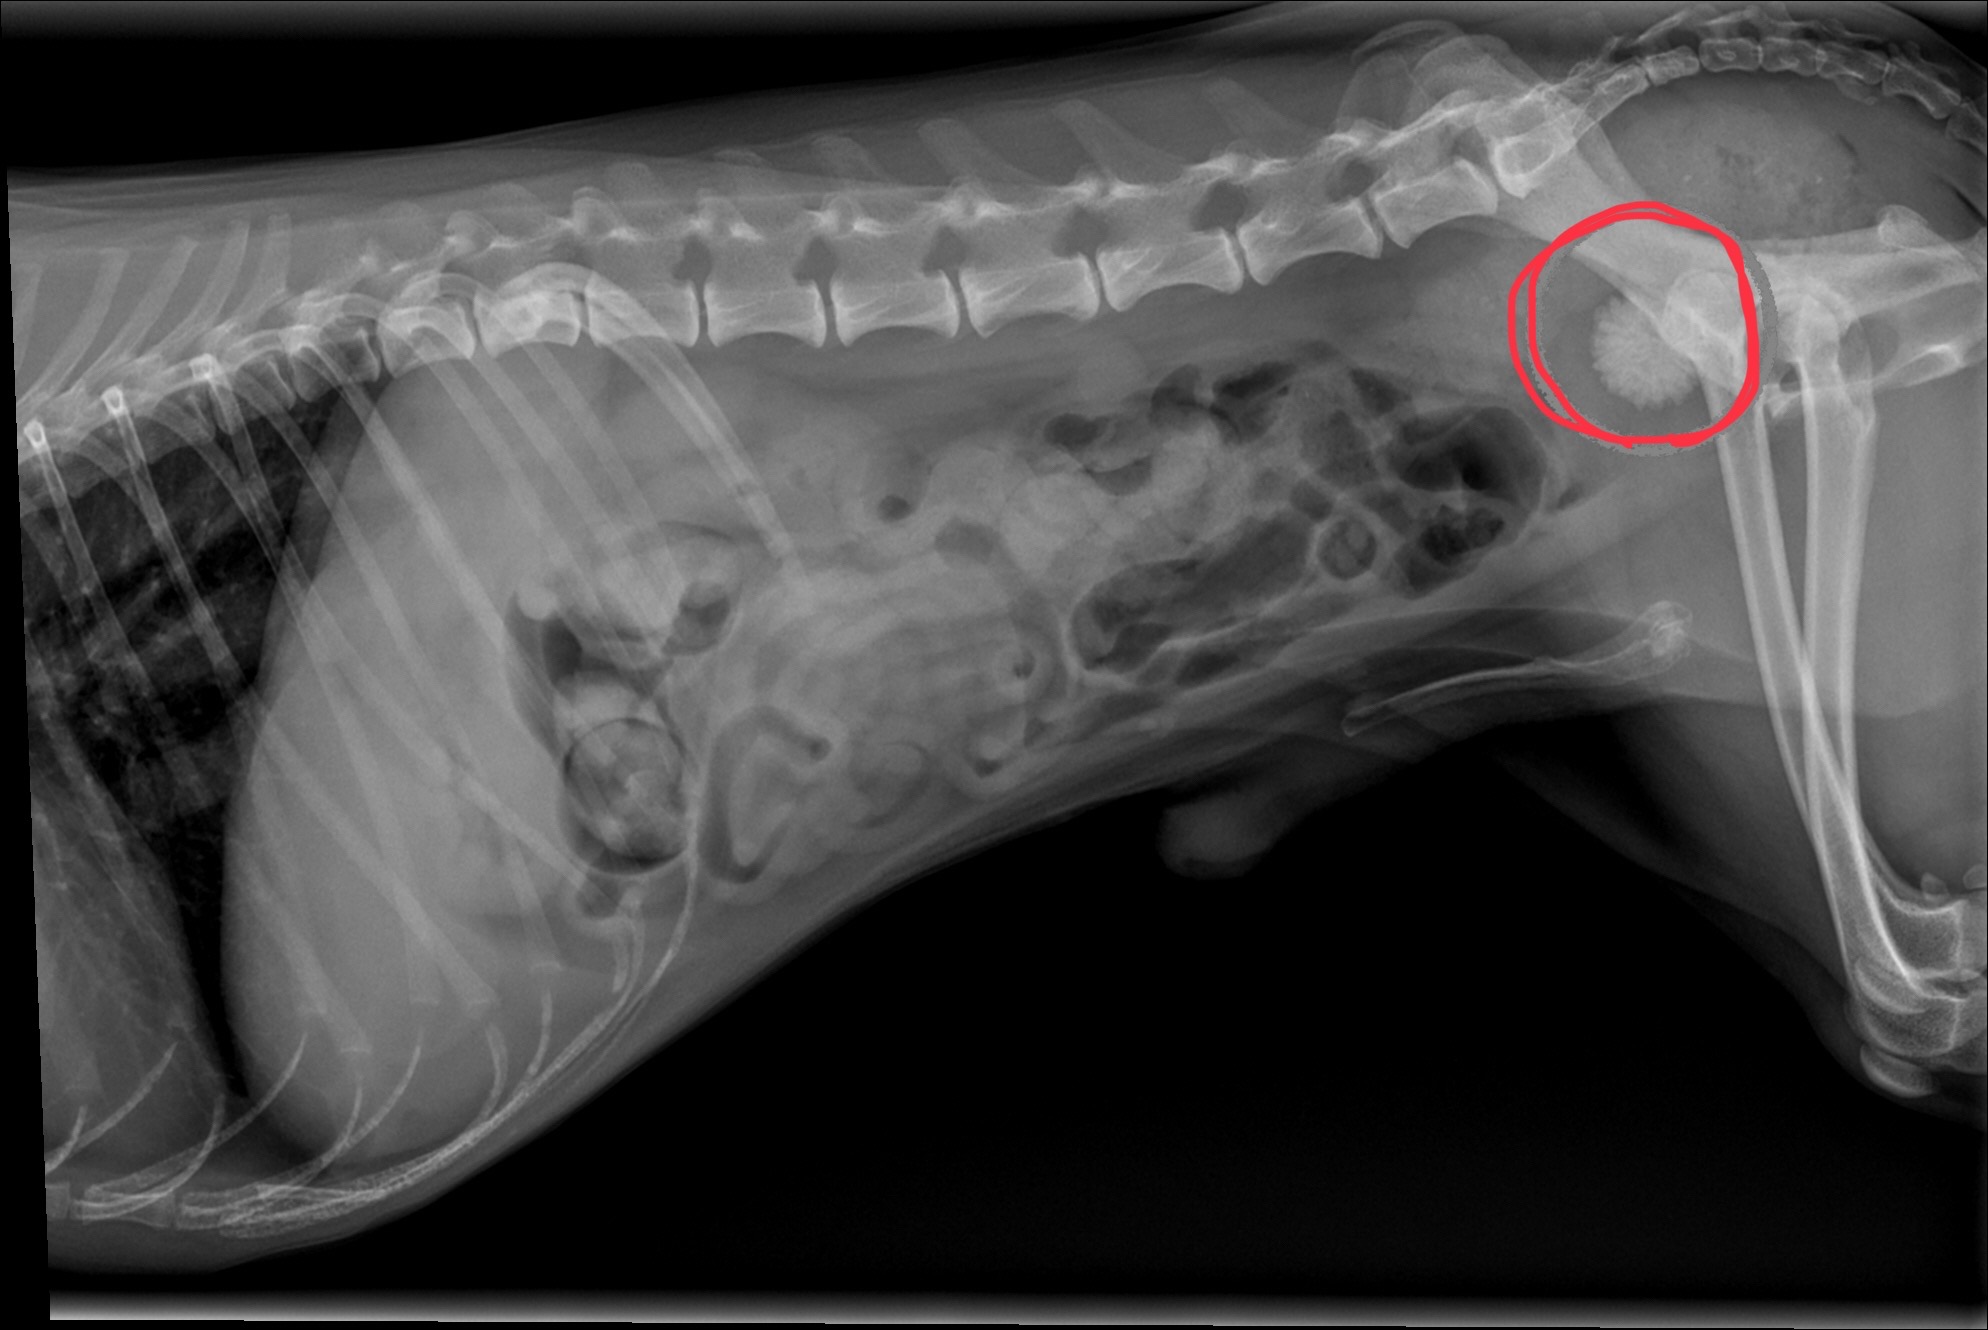

こんにちは!森のいぬねこ病院 芋沢院の榎原です☀️ 芋沢ではカメムシの舞う季節となってまいりました。。 退治に勤しむ日々が来そうです。 さて今日は…続きを読む